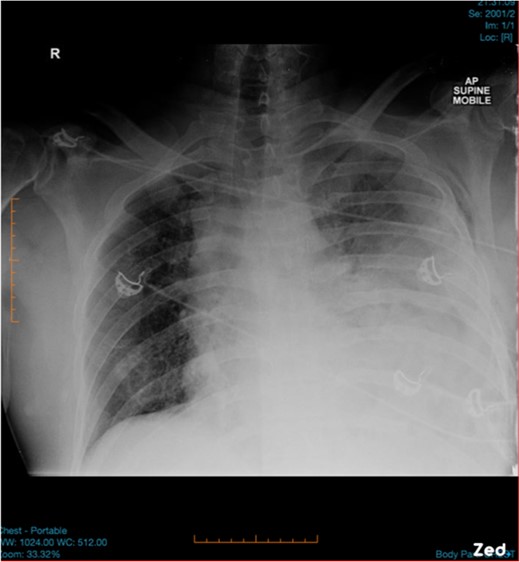

A 47-year-old male was brought to the Emergency department by ambulance after a high speed motor vehicle accident. On arrival, he had a Glasgow Coma Scale of 13, a patent airway with cervical spine collar in situ, spontaneous tachypnoeic breathing with an oxygen saturation of 97% on 15 l of oxygen. He had unequal breath sounds with decreased air entry on the left. He was tachycardic with a blood pressure of 110/70 mmHg. There were multiple bruises and abrasions to his torso and bilateral lower limbs. He had no previous medical history and was otherwise healthy. Initial chest x-ray was suspicious for a left-sided haemopneumothorax (Fig. 1) and an intercostal chest tube (ICCT) was inserted to the left side with a repeat x-ray confirming its position. However, there was minimal drain output and little swing. Subsequent computed tomography (CT) scan of the chest detected a left diaphragm rupture with a large diaphragmatic hernia where most of the left thorax was replaced by intra-abdominal contents (Fig. 2). A decision was made for emergency laparotomy to repair the diaphragmatic hernia. The patient was intubated in the emergency department prior to transfer to the operating theatre. While no ventilation problems were noted during transfer, the patient’s abdomen was seen to become progressively more distended to a point where it became tight and tympanic on percussion (Fig. 3). An underlying lung injury was suspected and the cardiothoracic team was called. At laparotomy, a significant pneumoperitoneum was confirmed with sudden escape of air upon entering the peritoneal cavity. The large hernia containing spleen, stomach and small bowel was reduced and the posterolateral diaphragmatic defect was repaired with a non-absorbable suture. This was followed by a left thoracotomy that identified a superficial laceration in the left upper lobe of the lung which was repaired with Prolene sutures and re-enforced with tissue glue. The patient was then transferred to the intensive care unit in a stable condition and made a good recovery. It is likely that the lung injury was caused secondary to intercostal catheter insertion during resuscitation in the Emergency Department. However, it could also have been secondary to associated left rib fractures or blunt trauma during the accident.

Coronal CT slide showing the entire left haemithorax being replaced by abdominal contents. Note the subcutaneous emphysema post ICCT insertion.